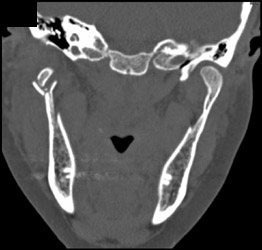

Carotid Stenosis